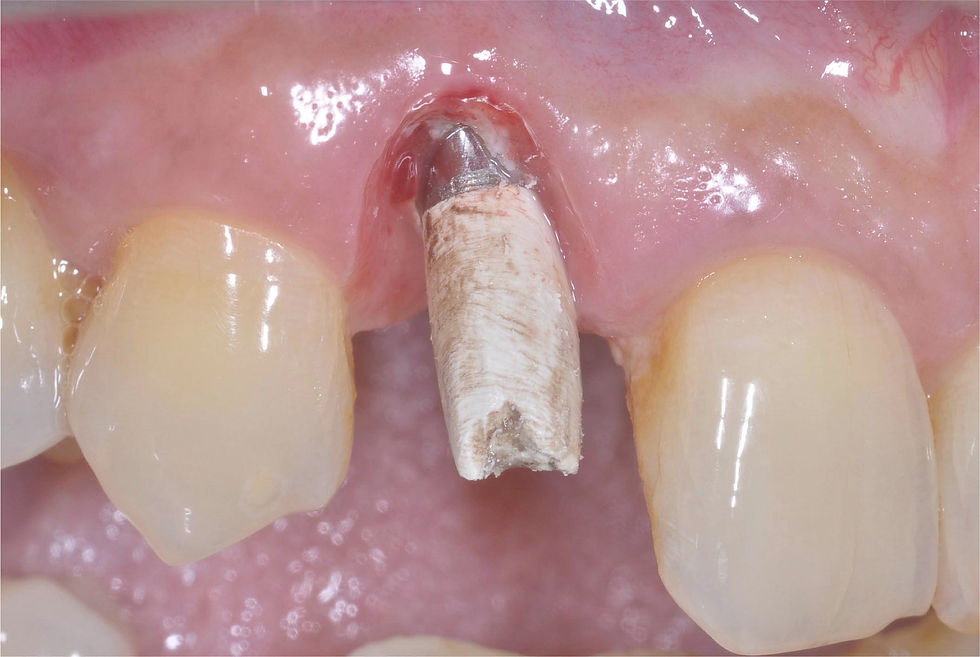

Insertion of the temporary PEEK abutment with titanium base, milled by the laboratory to obtain a feather edge morphology.

Relining and polishing of the temporary crown, whose morphology helps to stop the bleeding and consequently to stabilize the clot.